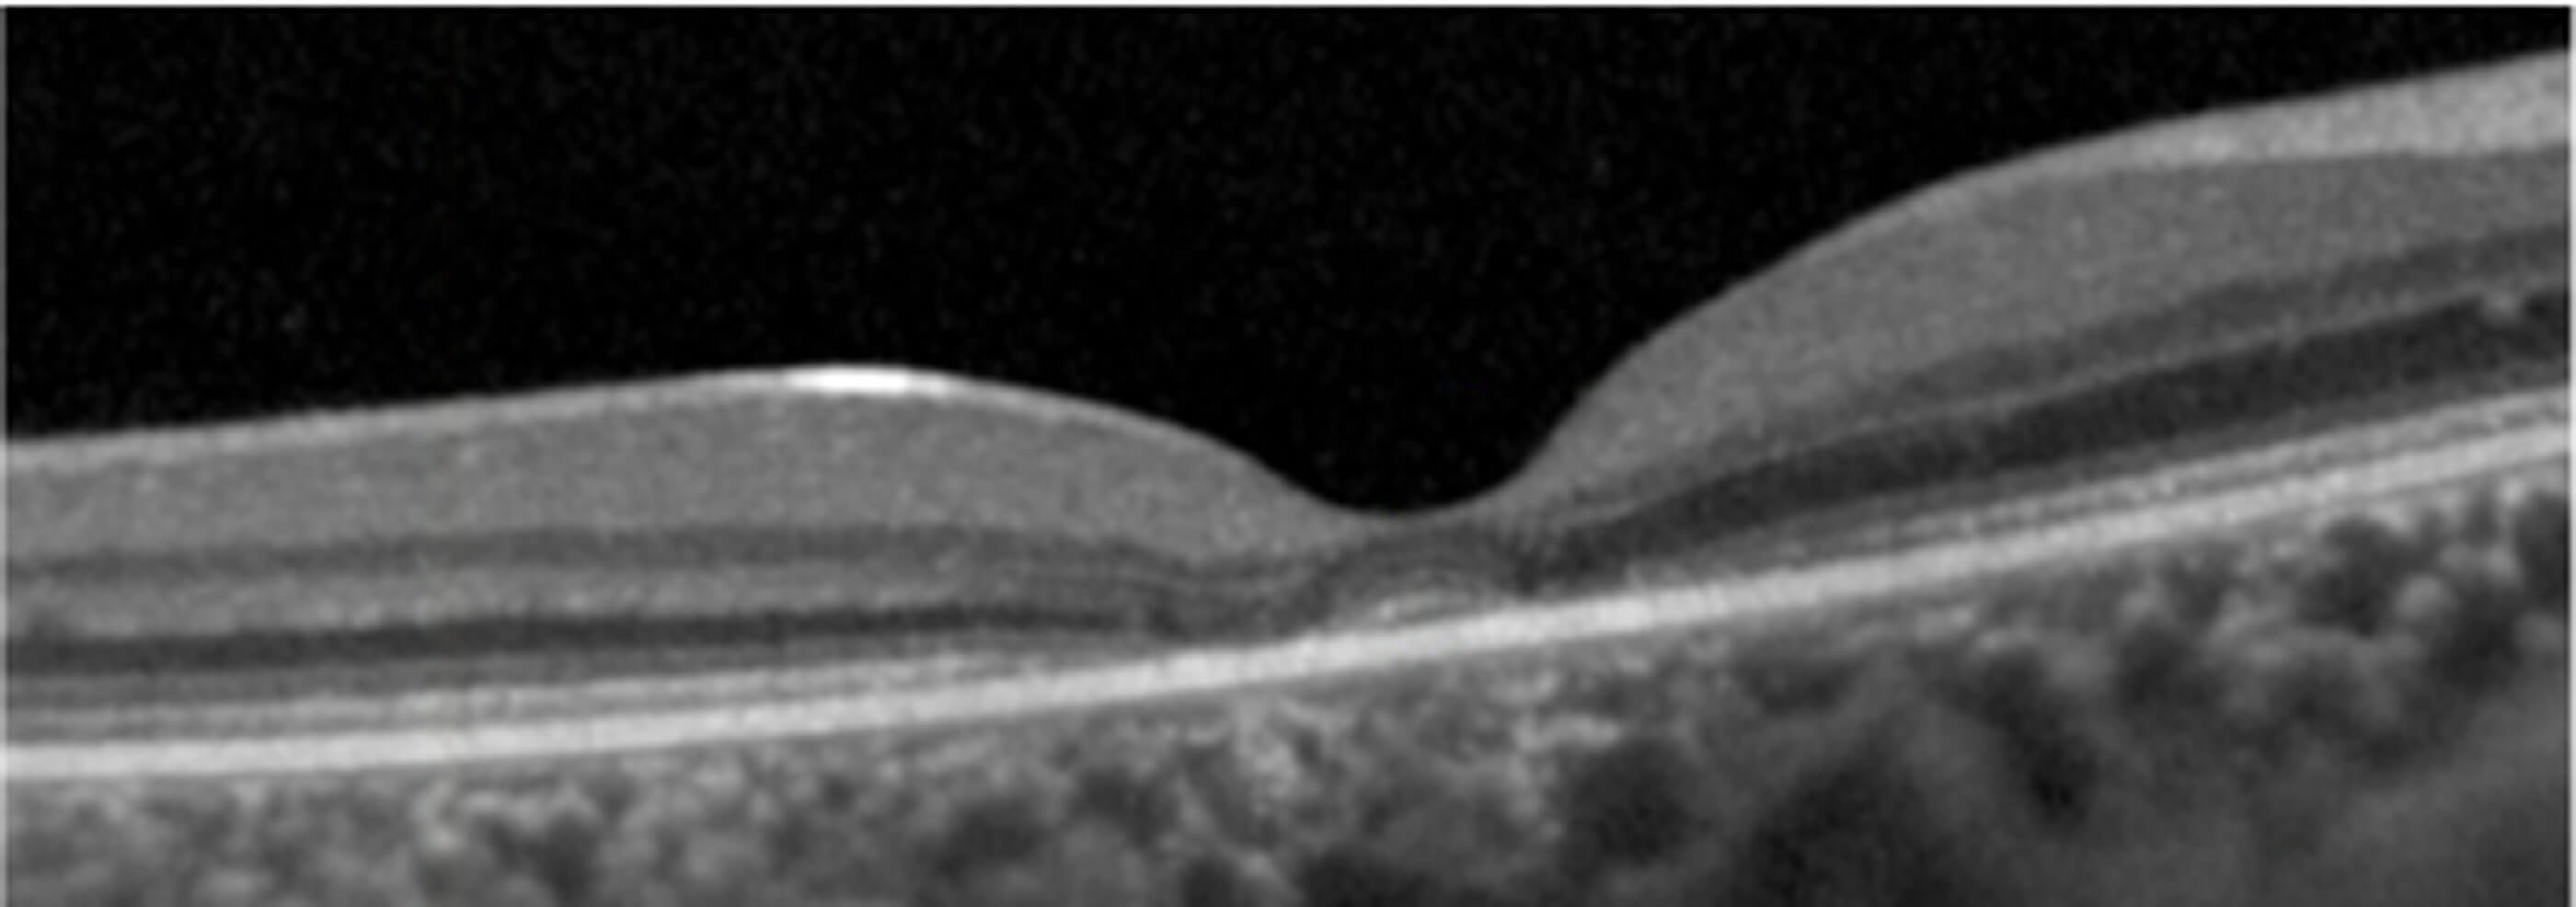

“CLN2 is a devastating diagnosis,” says Robert [1]. “Intraventricular infusion enzyme replacement therapy (ERT), where the drug is delivered directly into the cerebrospinal fluid, is an excellent treatment for slowing the loss of cognitive and motor skills associated with CLN2 disease, however children receiving this therapy continue to rapidly go blind. With optical coherence tomography (OCT), as the disease progresses, you see changes such as retinal thinning, loss of the photoreceptor layer, ellipsoid zone degeneration, and macular and optic nerve head atrophy.

“This disease is uniquely positioned for using OCT as an outcome measure for clinical trials since the degeneration or disappearance of the ellipsoid zone is closely linked to the decline in visual function. So, it was agreed that measuring ellipsoid loss is the ideal primary clinical endpoint for the trial.

Figures 2 & 3: Cropped Spectralis OCT and MultiColor images showing parafoveal

loss of ellipsoid and bull’s-eye maculopathy in patient with CLN2 disease.